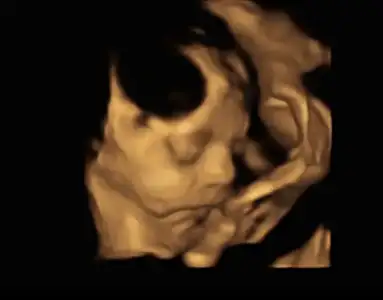

Slm kızlar bende kontrole gittim bugün bu ay çok yorduğum için kendimi endişeliydim ama çok şükür herşey yolunda, doktorum çok güzel orantılı büyümüş göbek dedi aşırılık yok dedi, 29+6 dayım ama bebiş 30+6 gözüküyor bir hafta önde devam, kilomuz 1640gr boy 42cm çok iri geldi bana ya, doktorum aynen devam harekete bol yürüyüş dedi, doğum sordum 8bin alıyormuş kendisi Medicana hastanesine gidip normal doğum+1gece yatış 4bin dedi şubatta artacakmış ama refakatçi ve eşe izin veriyormuş sadece ziyaretciye izin vermiyormuş ne süsleme ne fotoğrafçı izni yok vazgeçtim ordan başka hastane araştıracağız ama doğumhaneye kadar gösterdiler otel gibi hastane